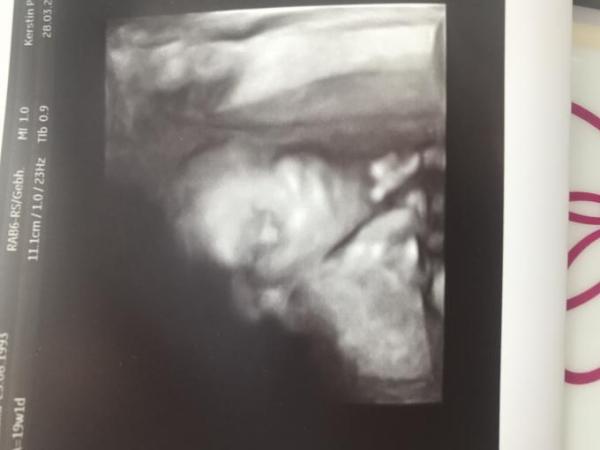

Heute beim fa alles super. Hatten ja den großen und alles war perfekt. bleibt bei Team rosa und sie liegt mit dem Kopf oben rechts, die Beine unten links, also quer im Bauch. ca. 21cm und 283g hat sie. Wir sind überglücklich

Ups Bild vergessen

Bild zu